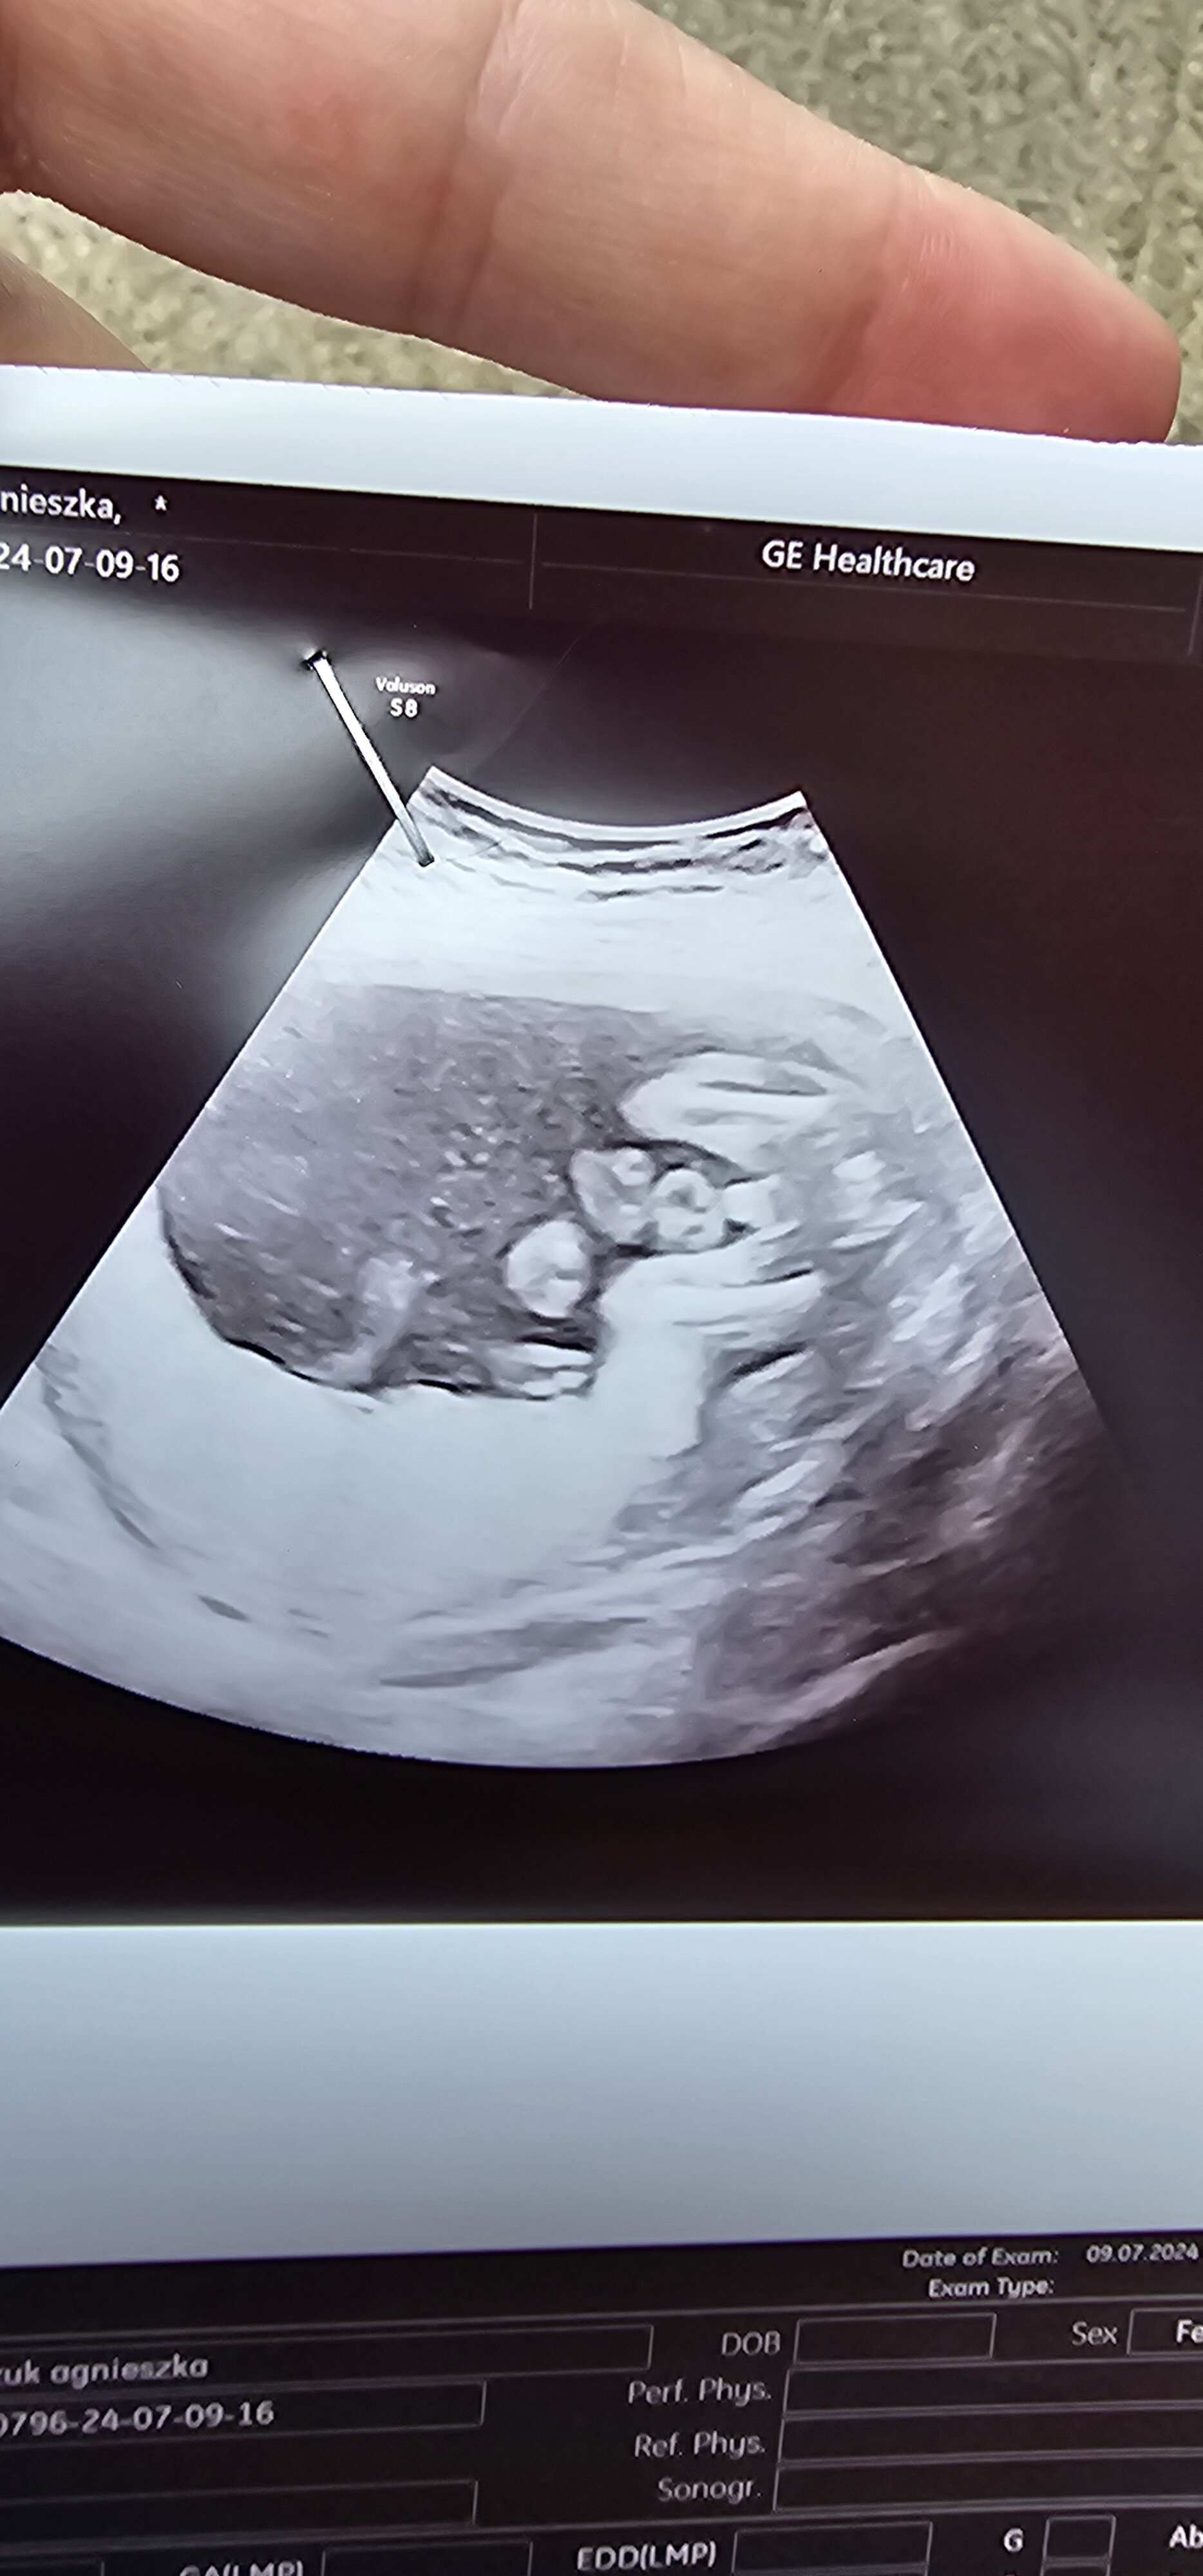

Hej dziewczyny, nie mam pewności co do płci, na pierwszych prenatalnych nie chciało się pokazać kim jest , strasznie się zakrywało , dzisiaj ginekolozka powiedziała że chłopiec, a wy jak myslicie?  mam już córkę, ale nie mam żadnego zdjęcia z usg córki. Jak wy uważacie co tu widać? Dodam iż to 20tc i mam tylko takie zdjęcie,szczerze nie znam się na USG , a chciałabym poznać każdej z Was opinie co tutaj jest

mam już córkę, ale nie mam żadnego zdjęcia z usg córki. Jak wy uważacie co tu widać? Dodam iż to 20tc i mam tylko takie zdjęcie,szczerze nie znam się na USG , a chciałabym poznać każdej z Was opinie co tutaj jest